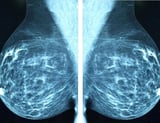

Breast cancer remodels lymphatic vessels to facilitate spread to draining lymph nodes and beyond, a process demonstrated by researchers from the University of Turku, Turku University Hospital and InFLAMES Flagship.

Early detection of breast cancer remains crucial, as it improves prognosis and treatment outcomes.

Breast cancer is still a major global health issue, with Finland reporting more than 5,000 new cases annually and five-year survival around 90%, underscoring the impact of early diagnosis and advances in treatment.